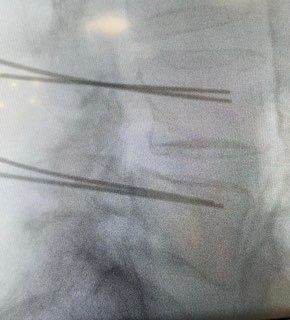

Starszy Asystent w Klinicznym Oddziale Neurochirurgicznym oraz Poradni Neurochirurgii Wojewódzkiego Szpitala Specjalistycznego im. św. Barbary nr 5 w Sosnowcu. Konsultant Kliniki Neurologii Szpitala Klinicznego nr 1 w Zabrzu. Absolwent Wydziału Lekarskiego Śląskiego Uniwersytetu Medycznego w Zabrzu. Staż podyplomowy odbył w latach 2010-2011 w Oddziale Neurochirurgii WSS nr 4 w Bytomiu. W 2018r. złożył egzamin specjalizacyjny po zakończeniu szkolenia w ramach rezydentury w WCM Opole. W 2019 roku uzyskał stopień doktora nauk medycznych. Specjalizuje się w kompleksowym leczeniu schorzeń kręgosłupa (dyskopatia, stenoza kanału kręgowego, kręgozmyk) oraz neuroonkologii. Szczególny zakres działań medycznych to nowoczesne, małoinwazyjne operacje kręgosłupa z wykorzystaniem technik endoskopowych (mikrodiscektomia - implanty rozprężalne), przezskórnych stabilizacji oraz mikrochirurgicznych dekompresji. Wykonuje procedury iniekcyjne; discoGEL, GelSTIX, kriolezje oraz blokady przeciwbólowe kręgosłupa odcinka szyjnego, lędźwiowo-krzyżowego a także stawów krzyżowo-biodrowych, które odgrywają istotną rolę w procesie diagnostyczno-leczniczym wielu zespołów bólowych. Na co dzień przeprowadza operacje w ramach kontraktu z NFZ. Członek Polskiego Towarzystwa Neurochirurgów oraz Polskiego Towarzystwa Chirurgii Kręgosłupa. Uczestnik wielu krajowych i zagranicznych kursów neurochirurgicznych, m.in. w Czechach, Słowacji, Niemczech, Włoszech, Danii, Austrii, Szwajcarii i USA. Autor licznych publikacji naukowych.

Zdjęcia i filmy